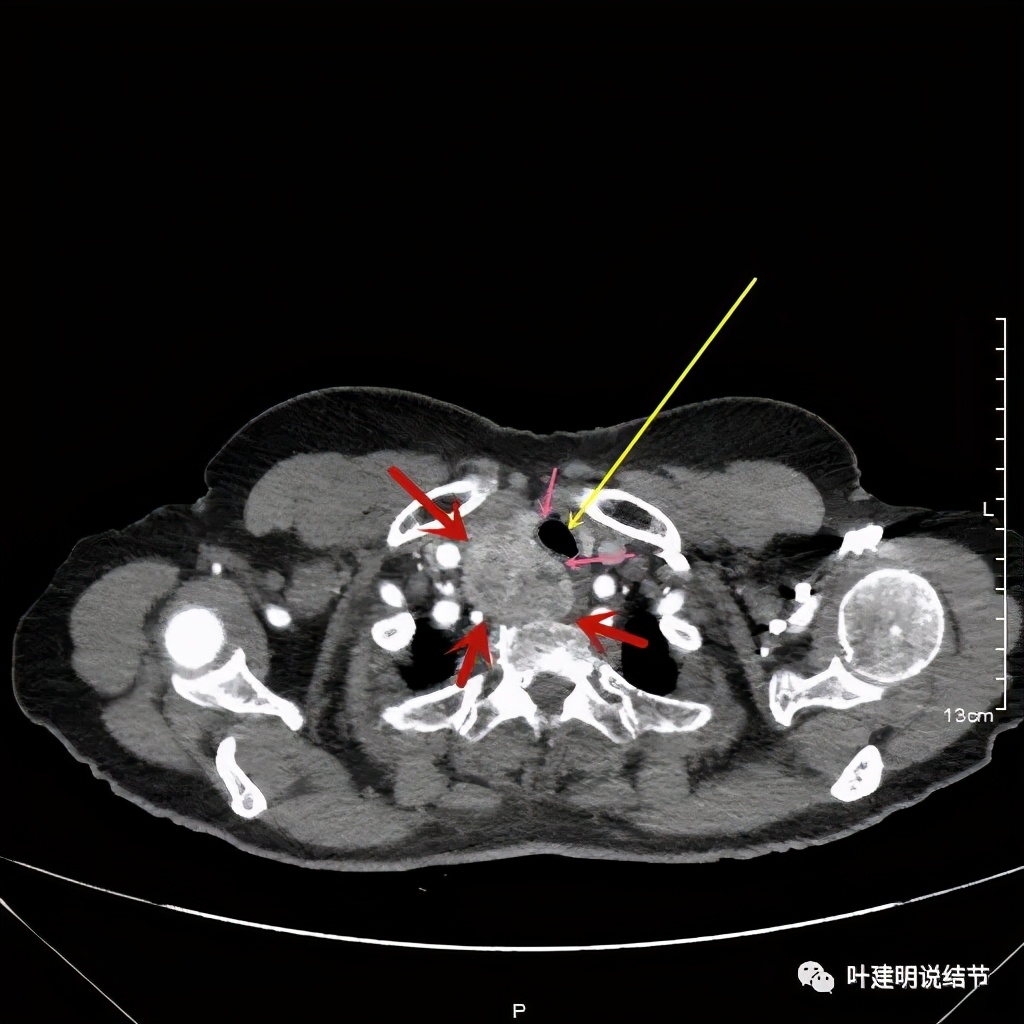

上图红色示肿瘤,黄色示气管,粉色示肿瘤与气管关系密切,而且肿瘤密度不均杂乱

上图红色示肿瘤,黄色示气管,而且肿瘤密度不均杂乱

上图红色示肿瘤,粉色示肿瘤与气管关系密切,而且肿瘤密度不均杂乱